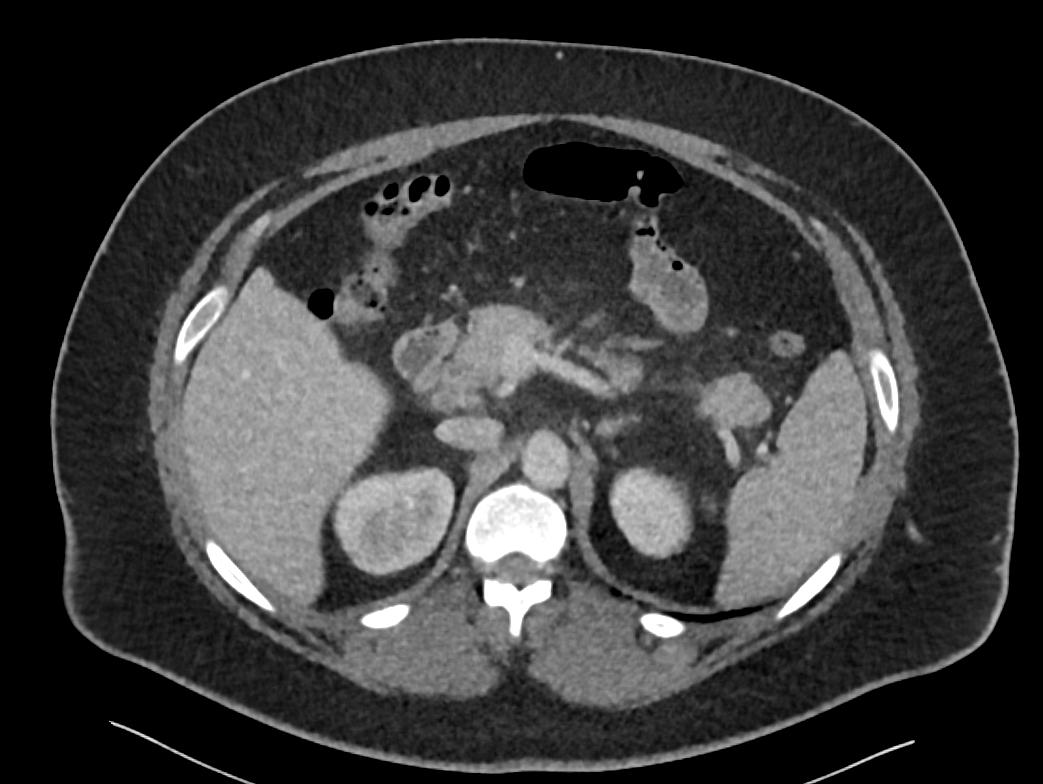

Patient: Padmakumar A. , *1988-04-24, PID: 3000069741773230809

Study Description: CT ABDOMEN

Image Series: Abdomen Ax 3mm [4]

<< Previous | Image 48 of 168 | Next >>